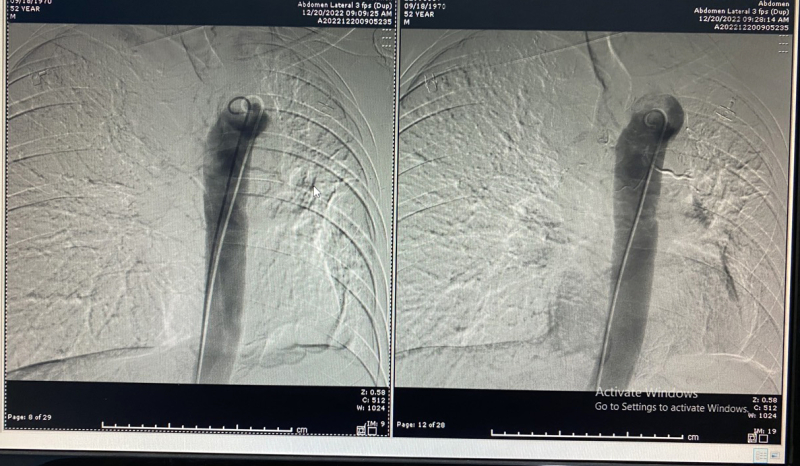

Ekip can thiệp của BSCKI Lê Tiến Hưng – Trưởng đơn nguyên can thiệp, điện quang can thiệp, Khoa Chẩn đoán hình ảnh, Bệnh viện Bãi Cháy đã tiến hành can thiệp nút mạch cấp cứu xử trí tình trạng ho ra máu cho bệnh nhân. Dưới hướng dẫn của hệ thống chụp mạch số hóa xóa nền DSA, bác sĩ điện quang can thiệp đã đã xử trí nút tắc các nhánh động mạch phế quản bị tổn thương, kiểm soát và chấm dứt được tình trạng ho ra máu cho người bệnh.

Quá trình nút mạch phế quản cầm máu cho người bệnh

Ca can thiệp diễn ra thuận lợi sau 30 phút thực hiện. Bệnh nhân được chuyển điều trị nội khoa tại Khoa Nội hô hấp – Bệnh viện Bãi Cháy để ngăn chặn và dự phòng tái phát ho ra máu. Hiện tại, sức khỏe bệnh nhân ổn định, phục hồi tốt.